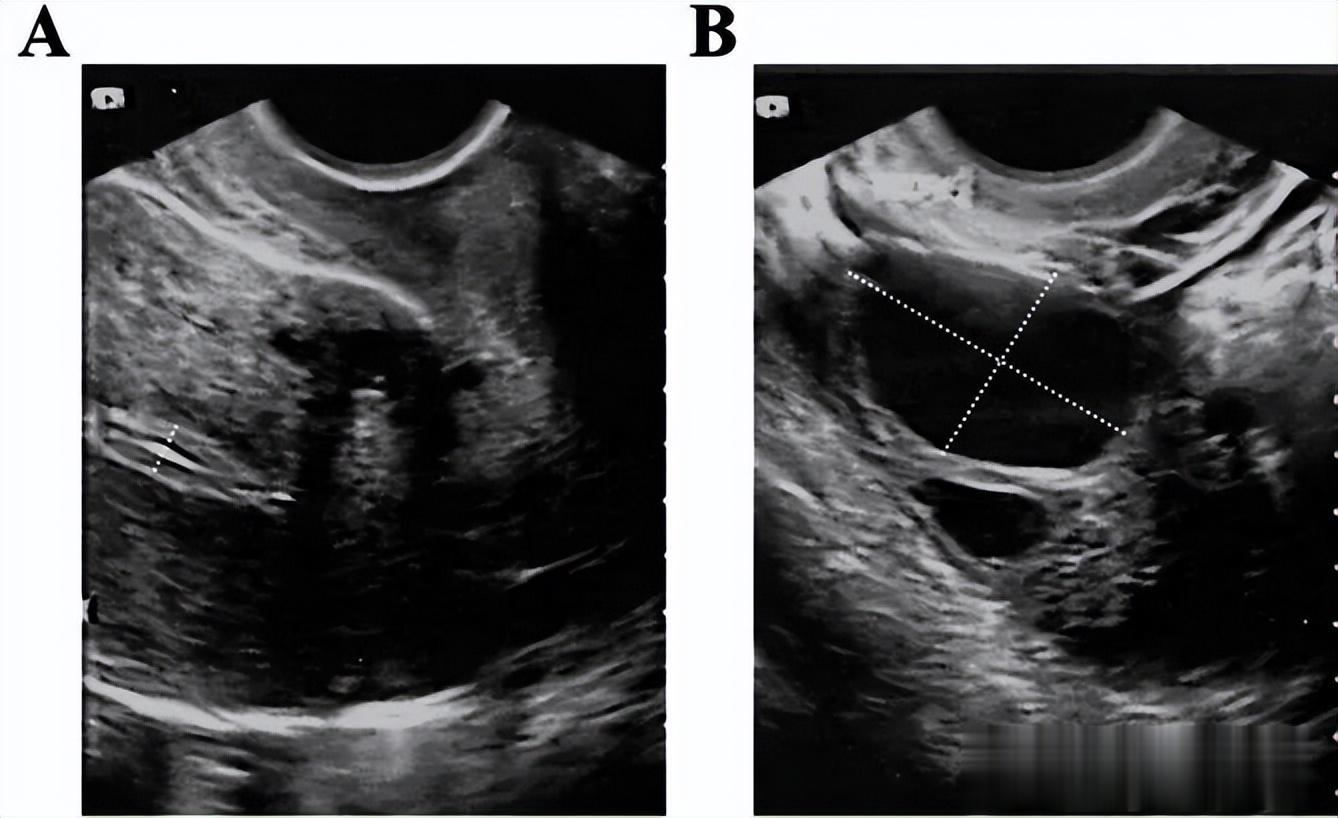

2022年11月至2023年3月期间,共行宫腔镜检查4次,前三次行粘连分离术,第四次检查宫腔形态正常。

患者做完粘连手术还放置了三角球囊支架(放置40天),在预防粘连方面发挥了作用。

另外用透明质酸凝胶隔开创面,也起到了一定的预防再次粘连的作用。